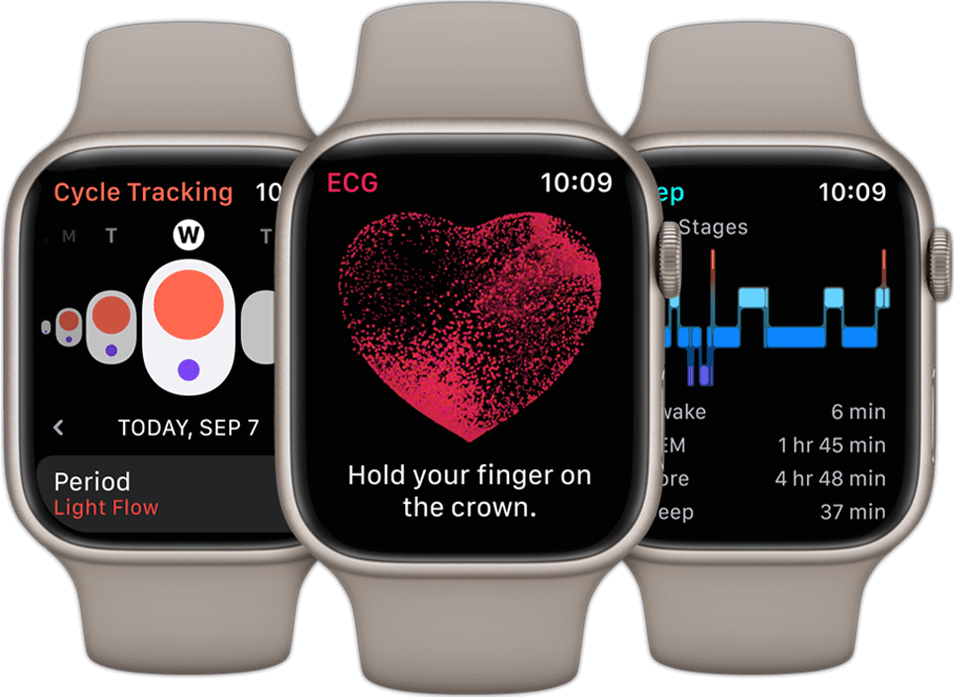

- Mõõda oma vere hapnikutaset võimsa anduri ja rakendusega.2

- Saa teateid kõrge või madala pulsisageduse ja südame rütmihäirete kohta2

- Unefaaside jälgimine võimaldab näha kui suure osa ajast olite igas unefaasis: peamises, sügavas ja REM-une faasis.

◊Cycle Tracking rakendus ei ole mõeldud kasutamiseks rasestumisvastase vahendina. Cycle Tracking rakenduse andmeid ei saa kasutada haiguste diagnoosimiseks.

1Temperatuuriandur ei ole meditsiiniseade ega ole ette nähtud kasutamiseks diagnoosimisel, ravil või mistahes muul meditsiinilisel otstarbel.

2Vere hapnikusisalduse rakenduse Blood Oxygen mõõtmistulemused ei ole ette nähtud meditsiiniliseks kasutamiseks, sealhulgas enese diagnoosimiseks ega arstiga konsulteerimiseks; neid peaks kasutama ainult üldise füüsilise vormi ja heaolu hindamiseks. Südame rütmihäirete teatiste saamiseks on vajalik watchOS-i ja iOS-i uusim versioon. Rakendus pole ette nähtud alla 22-aastastele kasutajatele või neile, kellel on diagnoositud kodade virvendusarütmia.